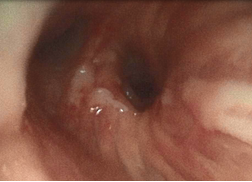

支气管镜:

隆突

左肺下叶开口

右中间支气管

5、左肺下叶支气管狭窄 肺癌?

10-20患者出现发热,支气管镜下:左肺下叶开口大量脓性分泌物伴气道痉挛

该患者为马尔尼菲篮状菌的重度感染,马尔尼菲篮状菌病为少见疾病。马尔尼菲篮状菌病(Talaromycosis,TSM)是由马尔尼菲篮状菌引起的侵袭性真菌病。该菌主要侵犯单核-巨噬细胞网状内皮系统,故而容易在淋巴结、肝、脾、肺、皮肤等发生病变。流行病学显示,90%以上病例出现在免疫力受损患者,尤其是艾滋病患者的免疫功能进一步下降,加剧了马尔尼菲篮状菌播散。TSM的影像学表现多种多样,包括大片实变、结节、磨玻璃改变、粟粒样病变、肺门或纵隔淋巴结肿大、胸腔积液、空洞、坏死,以及细菌性肺脓肿,内壁光滑,甚至有气液平面。气管镜下为气道内壁光滑的凸起结节,伪膜、溃疡等少见。